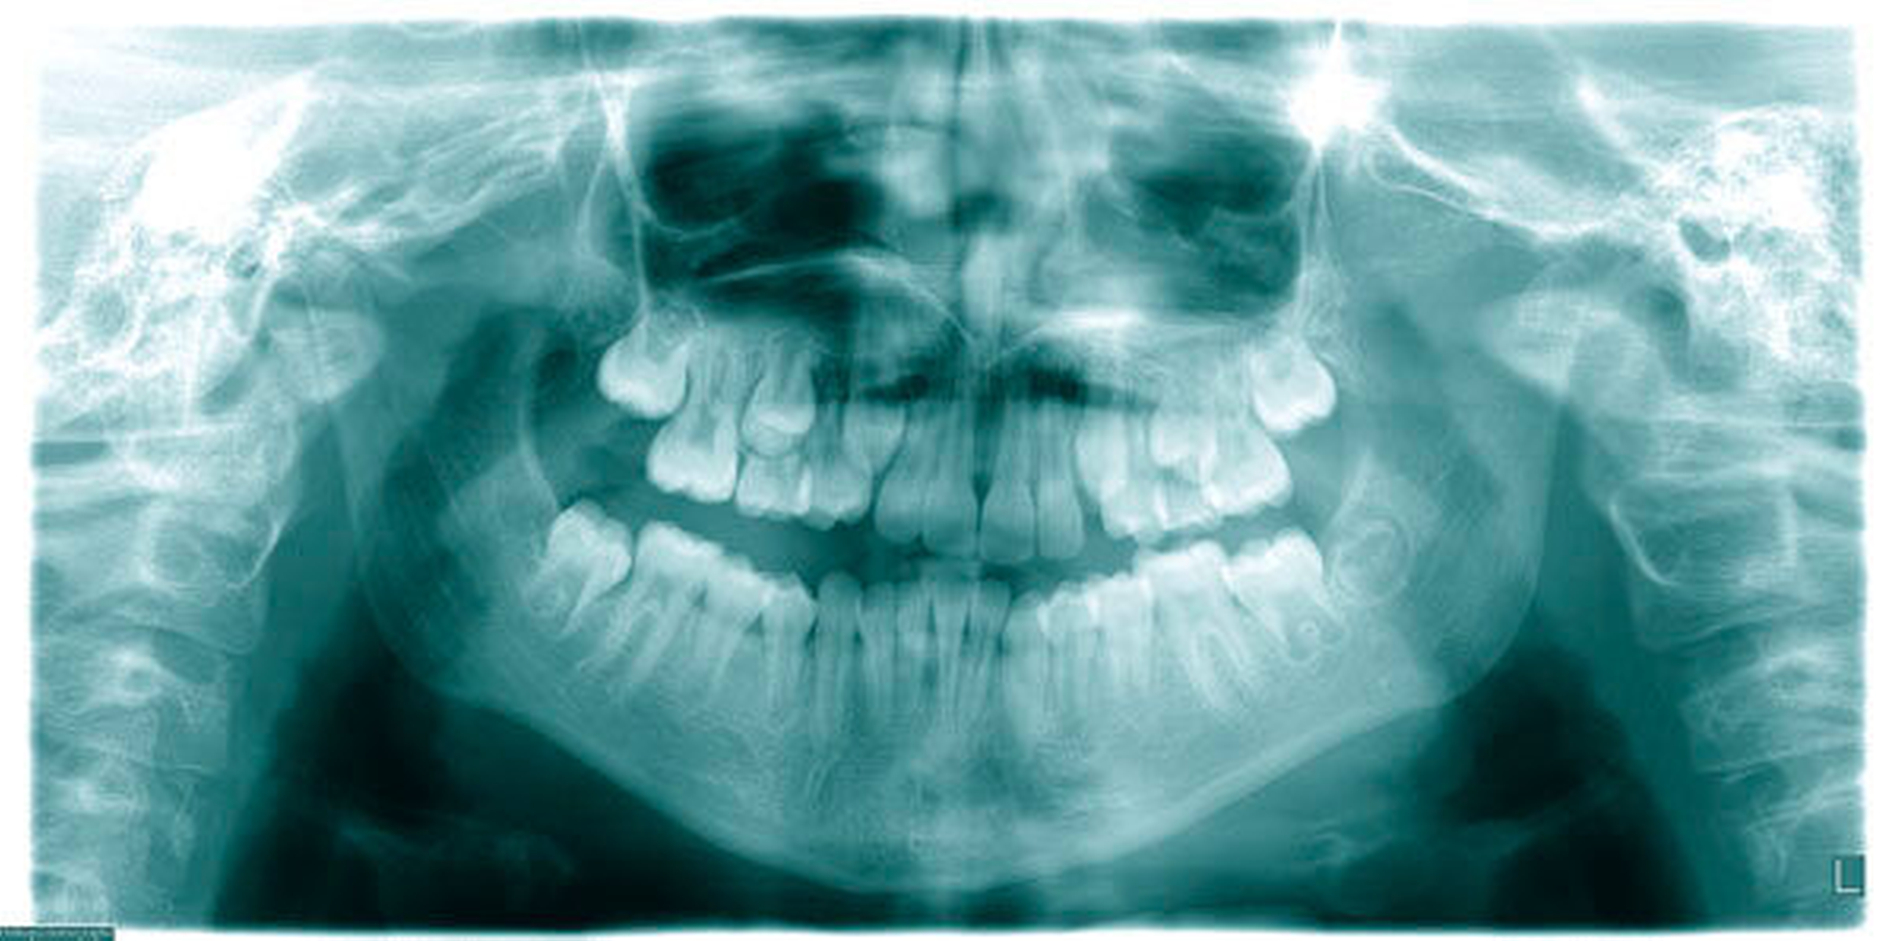

Wie beim Einbringen von Zahnimplantaten schaffen die computergestützte Planung und die Verwendung von Schablonen auch bei der Insertion von Mini-Implantaten mehr Sicherheit für den Behandlungserfolg. Für die zunächst virtuelle Insertion werden ein Abdruck oder ein Scan sowie ein Röntgenbild (FRS oder DVT) überlagert [De Gabriele, 2017] (Abbildungen 1 und 2, Easy Driver Software, Labor Uniontech, Parma/IT). Während in einem normalen Fall das FRS ausreicht, ist bei schwierigen Situationen (zum Beispiel LKG-Spalte, palatinal verlagerte Eckzähne) sicherlich die Anfertigung eines DVTs empfehlenswert. Basierend auf der computergestützten Planung wird eine Insertionsschablone per Rapid-Prototyping-Verfahren (RKS Labor, Rastede/D, Abbildung 3) zusammen mit dem gewünschten kieferorthopädischen Gerät im zahntechnischen Labor hergestellt.

Das Prinzip einer CAD/CAM-gesteuerten Insertion wird anhand einer zehnjährigen Patientin mit einem Platzmangel für die oberen Eckzähne dargestellt (Abbildungen 4a, 4b). Die Behandlung begann mit dem Anpassen von Molarenbändern und einem Silikon-Abdruck des Oberkiefers, der mit dem FRS an das zahntechnische Labor gesendet wurde und dort mit dem FRS der Patientin überlagert wurde. So konnten geeignete Insertionsstellen virtuell geplant werden (Abbildungen 1, 2a, 2b). Nach Rücksprache mit dem Behandler bezüglich der Mini-Implantatpositionen erfolgte die Herstellung der Insertionsschablone (Abbildung 3). Parallel dazu wurde auch der Beneslider [Wilmes, 2010] hergestellt, der zusammen mit der Insertionsschablone geliefert wurde (Abbildung 5). Mithilfe der Insertionsschablone konnten die Mini-Implantate und der Beneslider im selben Termin eingesetzt werden (Abbildungen 6, 7a, 7b). Nach 10 Monaten Distalisierung waren die Molaren in der Zielposition und es war ausreichend Platz für die Eckzähne vorhanden (Abbildungen 8a, 8b), so dass Brackets für die zweite Phase der Behandlung eingesetzt werden konnten. Die Multibracket-Apparatur (Abbildung 9) konnte nach 12 Monaten entfernt werden (Abbildungen 10, 11).